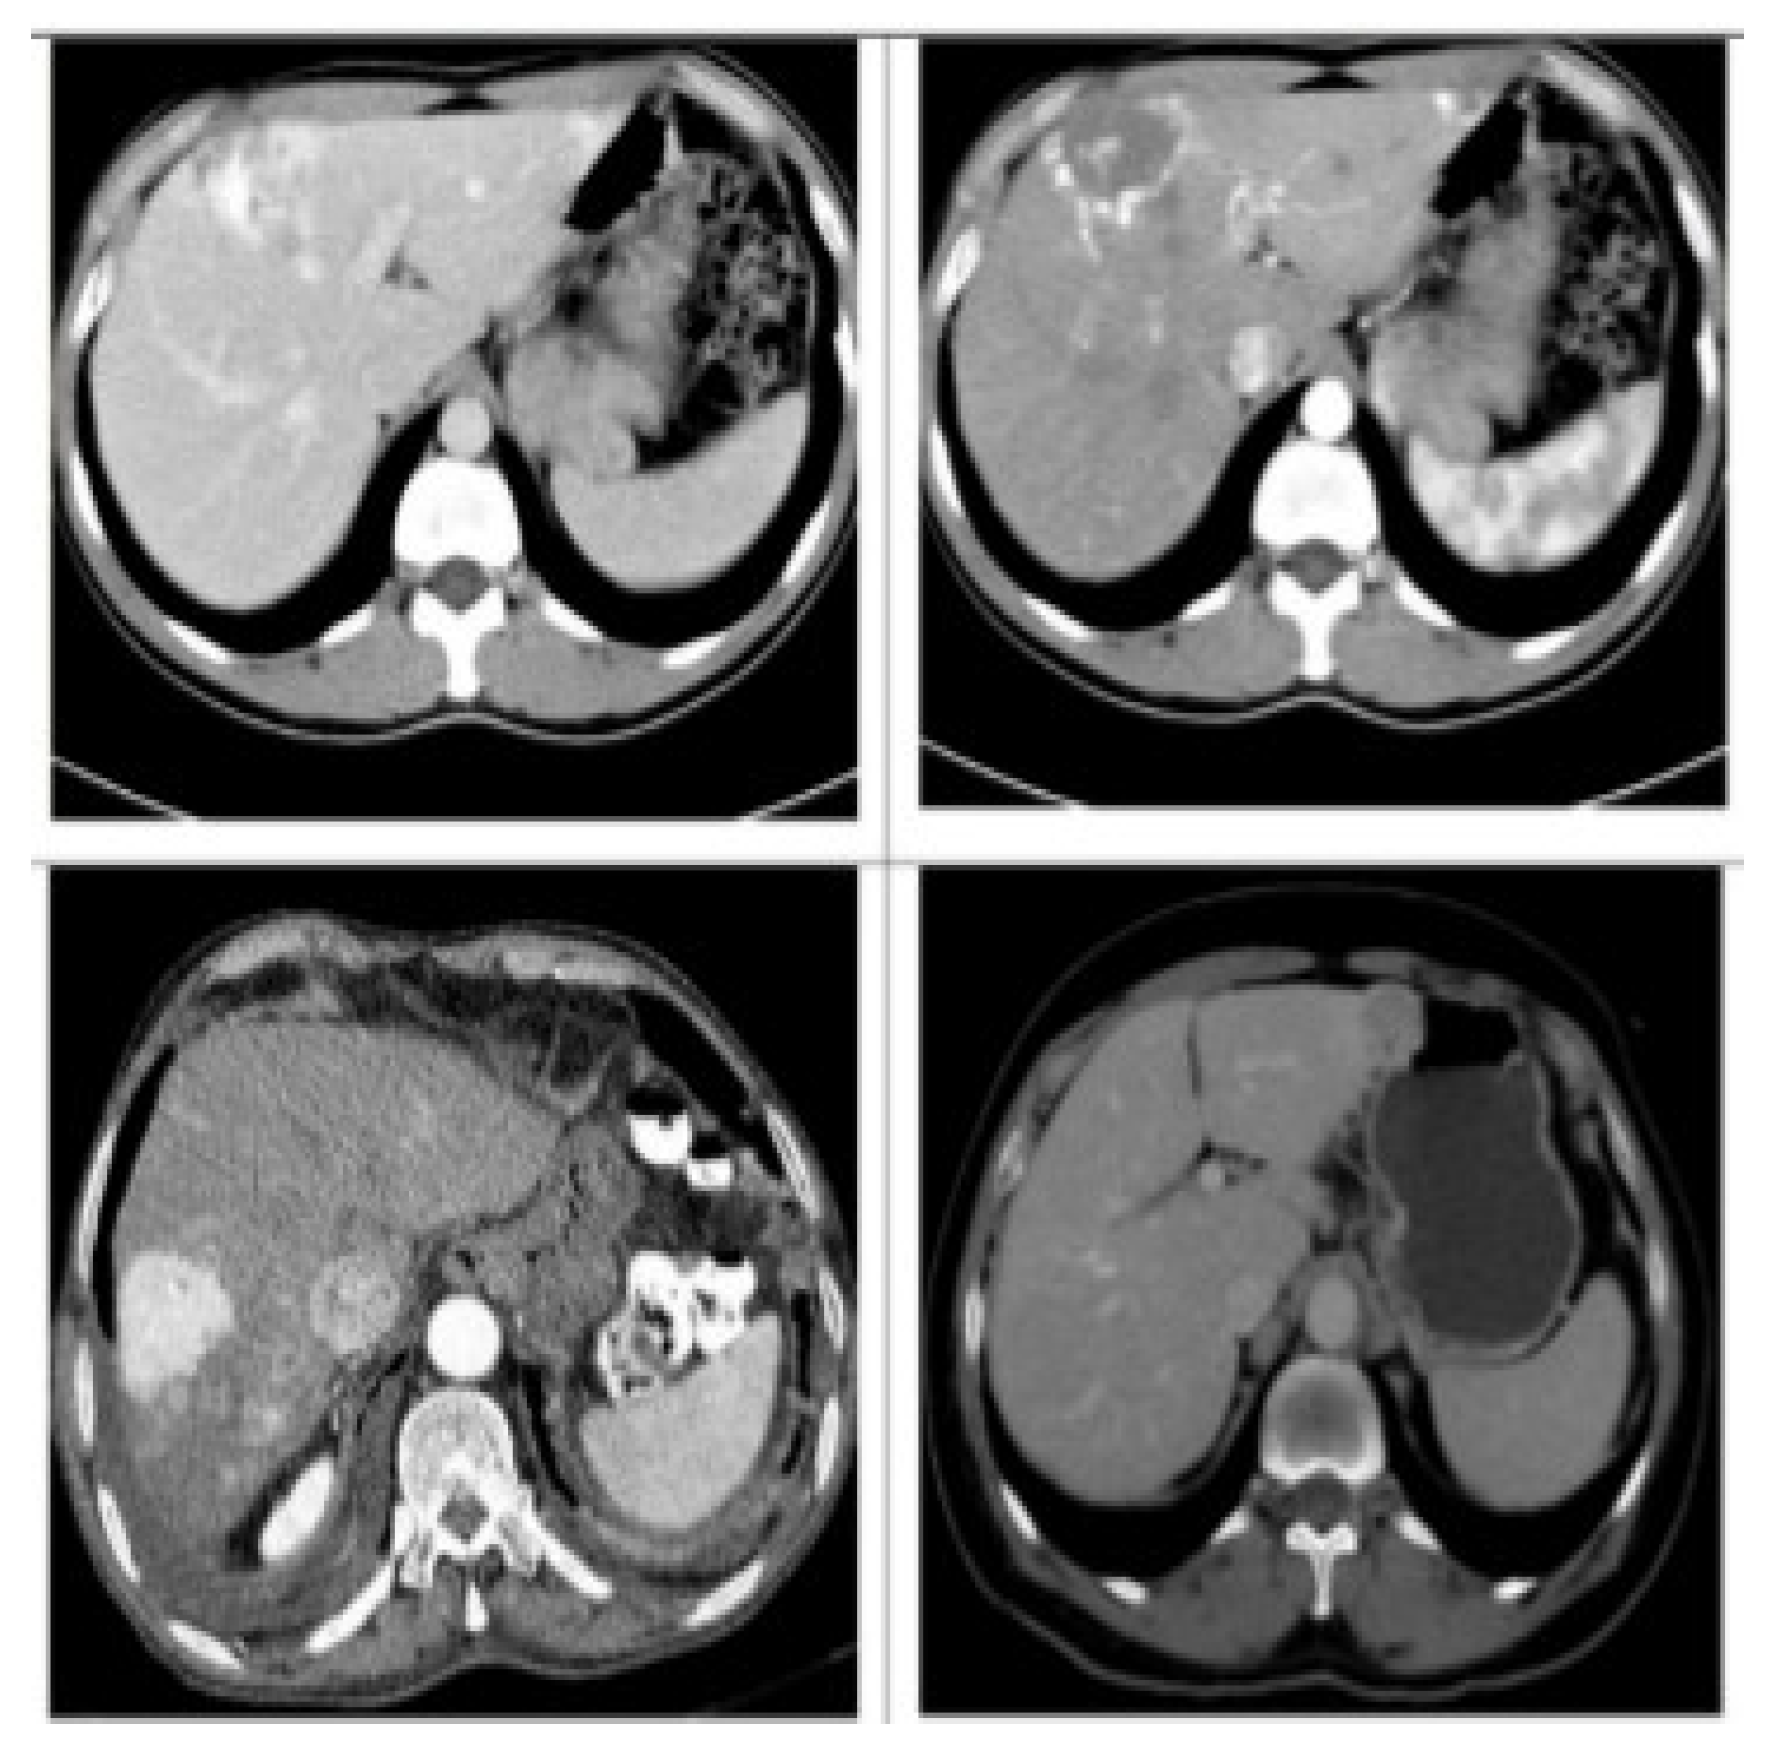

In this paper, the CT image dataset of liver lesions that were used in the study was collected from Jiangbin Hospital, an affiliated hospital of Jiangsu University (from 2015 to 2018), by searching for the medical records with hepatocellular carcinoma, metastases, hemangiomas, and healthy tissues. This work included data from 120 different patients, 30 patients with one or multiple HCC, 26 patients with one or multiple Hema, 23 patients with one or multiple Meta and 41 Heal. The dataset contains a total of 4142 images, including 1040 images of HCC, 1036 images of Hema, 1032 images of Meta, and 1034 images of Heal. From each class, 250 images were randomly selected for testing dataset, and the rest images were considered as the training dataset. Figure 5 shows the CT image samples of each lesion. An expert radiologist was in charge of marking the margins and to determine the corresponding diagnosis which was established by biopsy. Figure 6 illustrates a set of data samples from the different types. Liver lesions are different in size, shape and contrast. We preprocessed the raw in Digital Imaging and Communications in Medicine (DICOM) CT images 512 × 512-pixel metrics with a slice collimation of 5–7 mm, and 0.57–0.89 as an in-plane resolution range of slice. We have truncated the CT scan Hounsfield units (HU) values, and we normalized all slice intensities into the range [0, 1] with min–max normalization.

Figure 6.

Dataset examples.